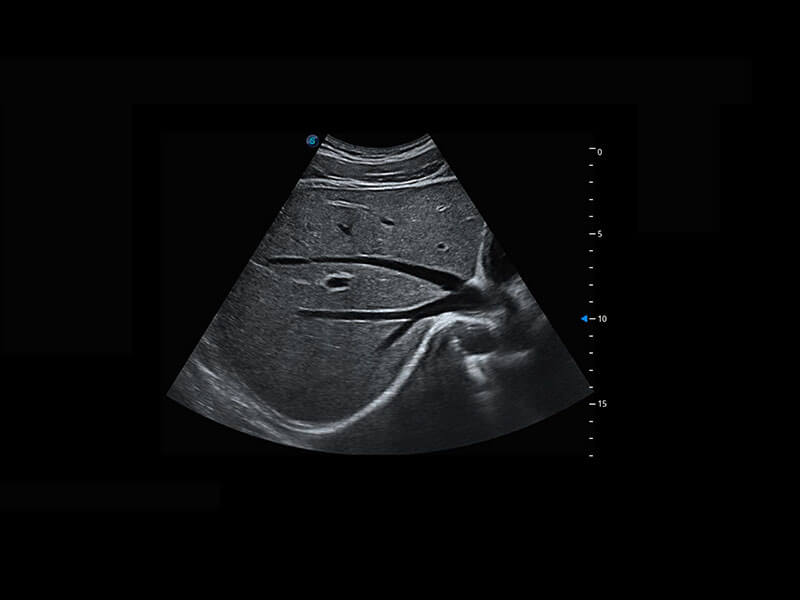

中晚孕筛查

P60提供简单易学易用的高端诊断工具,为您中晚孕筛查提供快速清晰的解剖信息。

1 OFD(HC): 87.03 mm

HC: 251.00 mm

GA: 27w 1d

HC/AC: 96.13 %

2 BPD: 70.56 mm

GA: 28 w 2d